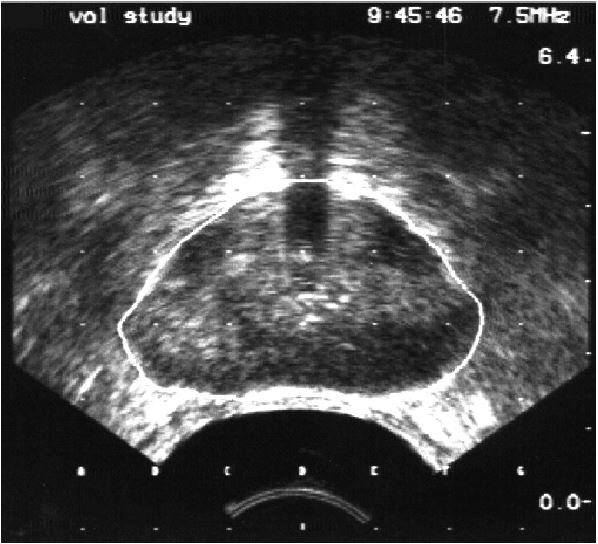

For the volume study a transrectal ultrasound probe is inserted into the rectum, and several images are taken of your prostate gland. These images provide a 3D model of your prostate gland. This model is used to decide how many Iodine-125 seeds are needed to treat you and exactly where they should be placed.